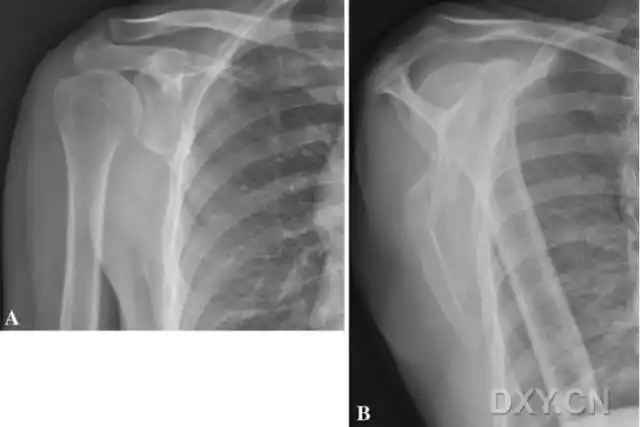

肩关节疼痛肩关节正侧位平片未见明显异常

corr临床对照研究:移位性肩胛骨骨折的非手术与手术治疗效果相似

直举性肱骨脱位:罕见的肩关节脱位,肱骨头向下异位,而胳膊上举.